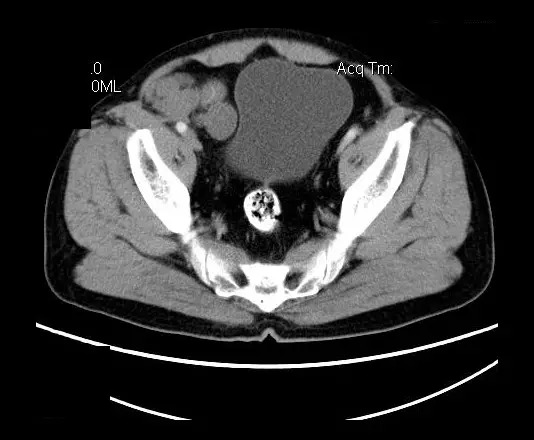

【影像表现】

盆腔右前侧及邻近腹股沟区可见多发大小不等的聚集生长的结节影,病灶呈软组织密度,边缘尚规整,分界尚清,增强扫描可见不均匀强化。膀胱局部受压,盆腔未见明显肿大淋巴结影。

“盆腔”多发性神经鞘瘤